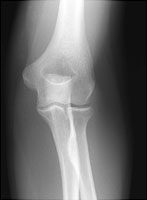

Radial head fractures are common and result from a fall on an outstretched hand. These fractures can be subtle and indirect signs are used to infer their presence. A visible posterior fat pat is the most sensitive indicator of an occult fracture. The "sail sign" or displaced anterior fat pad is also used to diagnose occult radial head fractures, but is less sensitive than displacement of the posterior fat pad.

- Click on the image for a larger versionBAP radiograph of the elbow. This demonstrates the subtle fracture of the radial head.